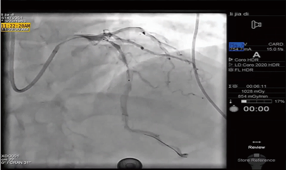

手术协同

急诊PCI/ CABG / 外科手术 / …

远程直播同步指导...

影像诊断

心电图 / 心脏彩超 /心血管造影影像 / …

远程协诊远程会诊...